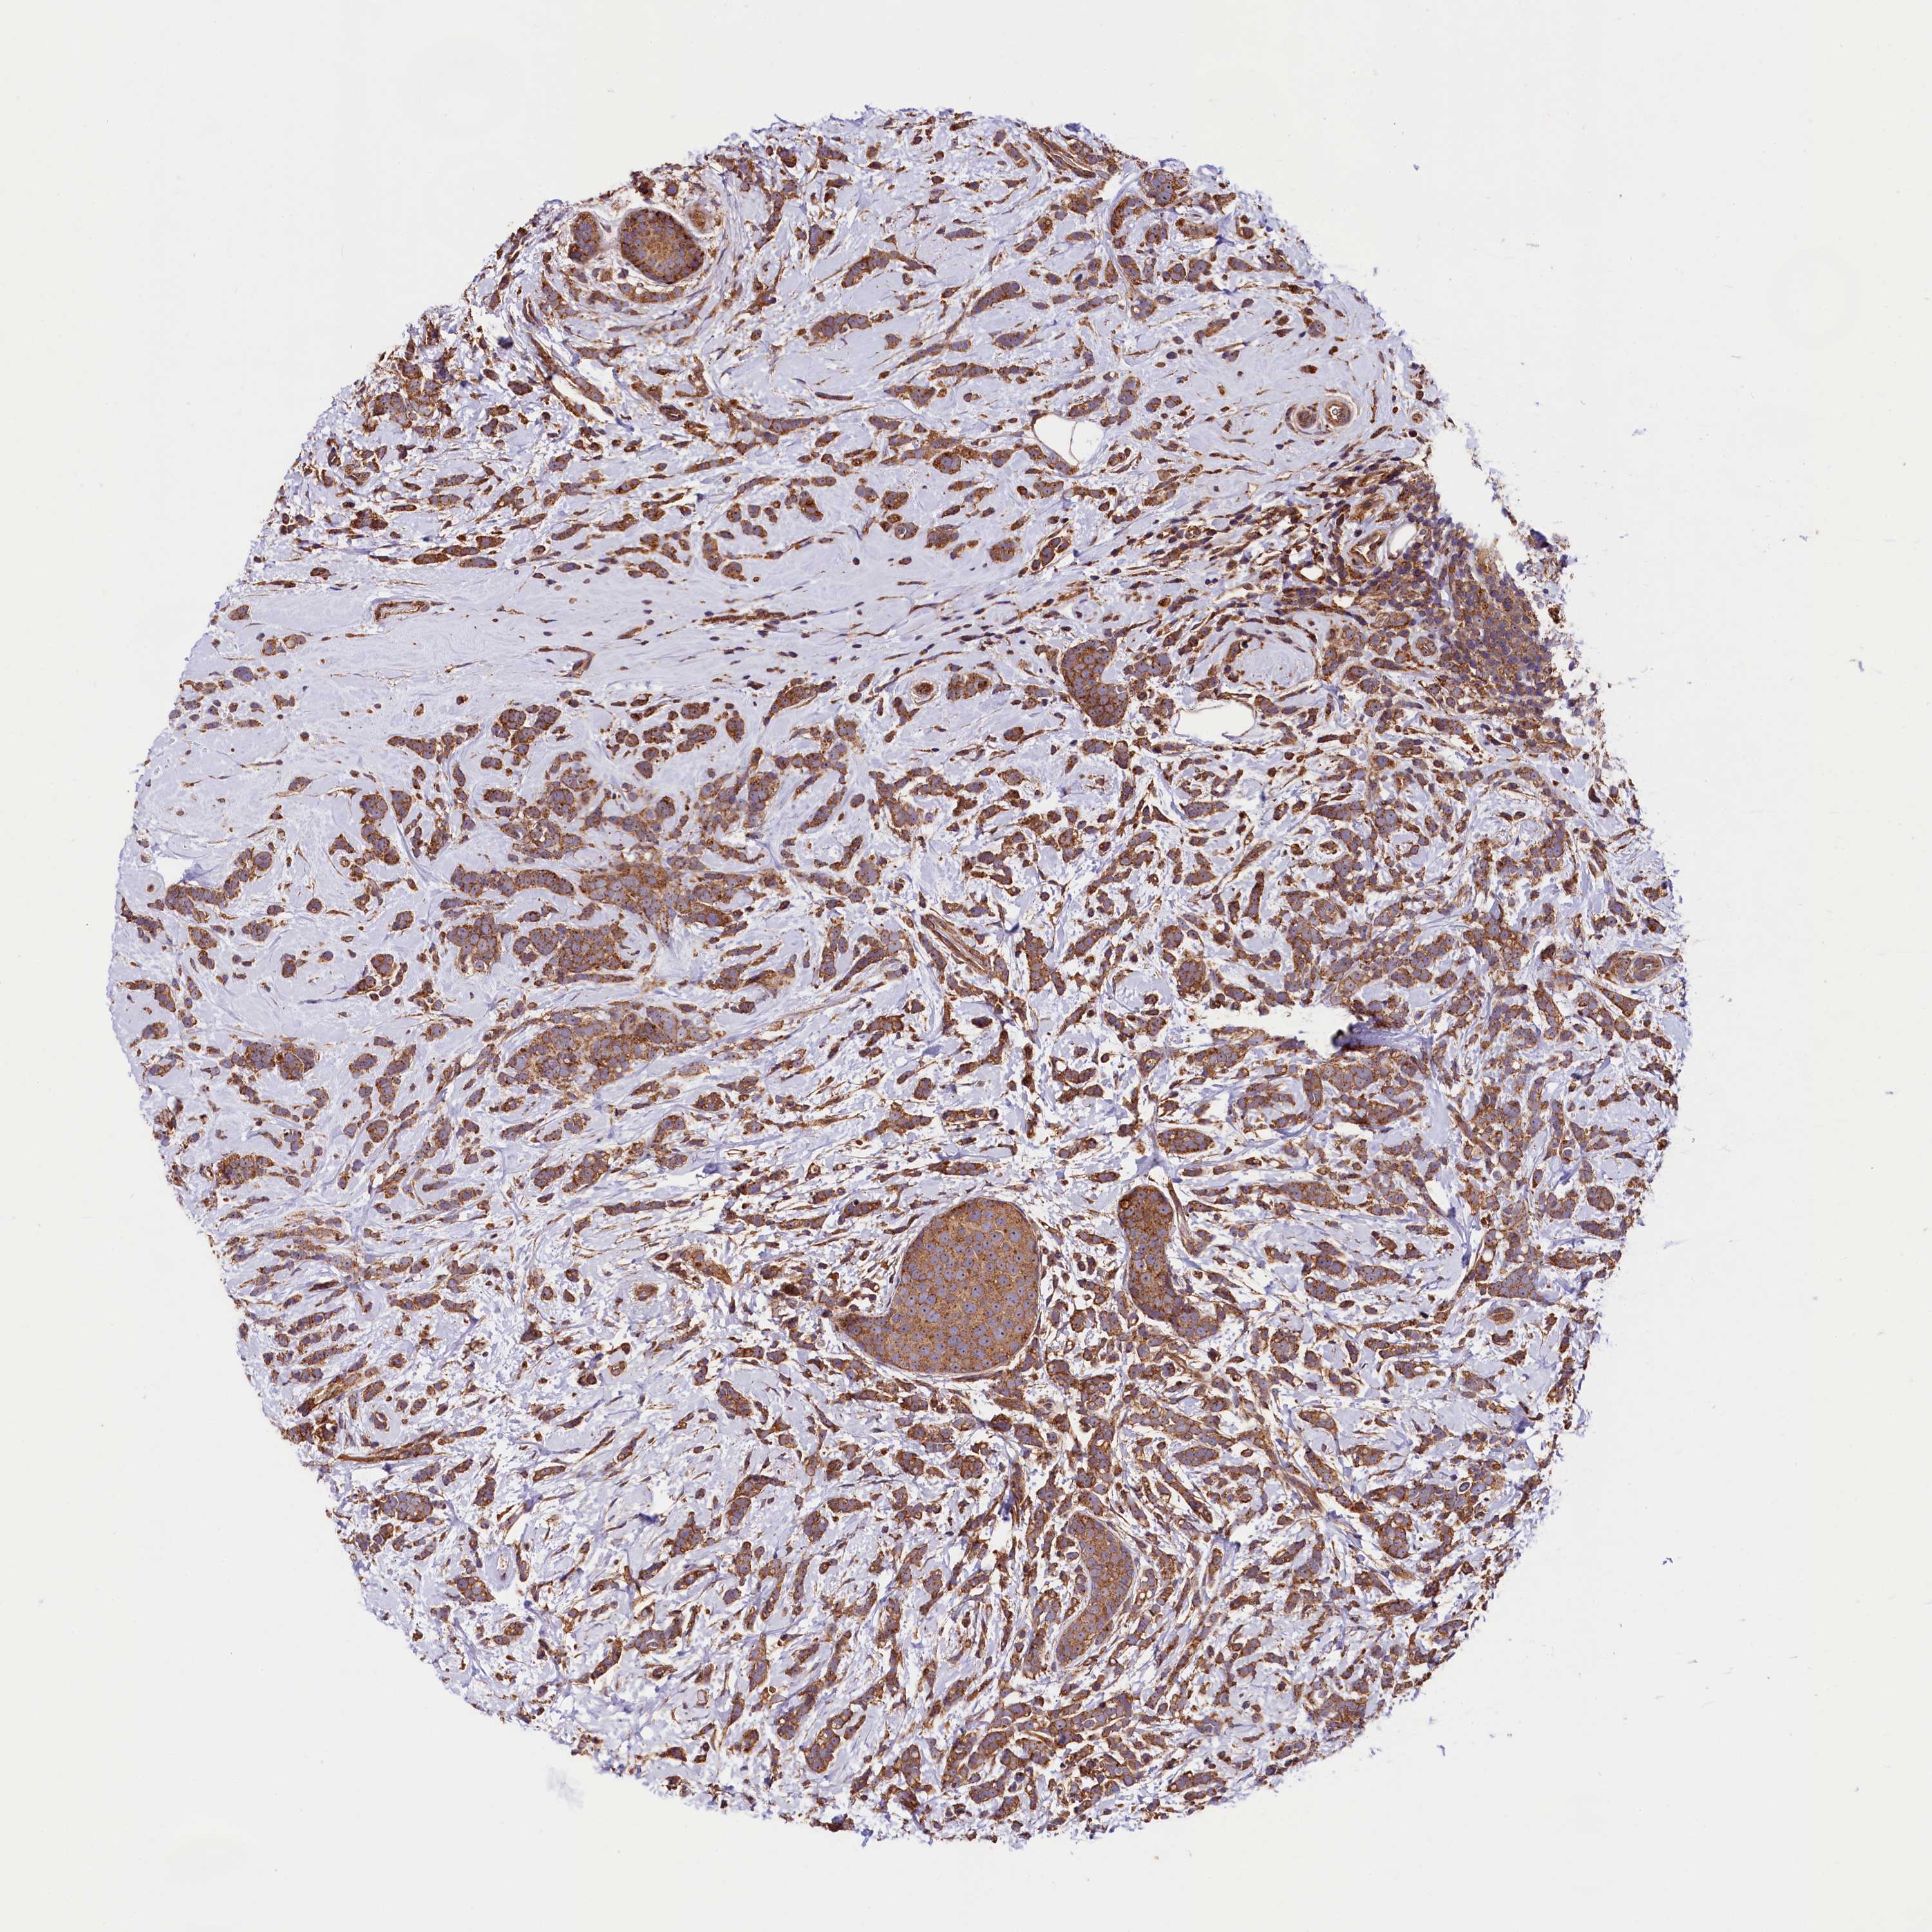

CANCER BREAST CANCER Show tissue menu

BRCA TCGA BRCA VALIDATION PROTEIN EXPRESSION

Breast cancer

Human cancer